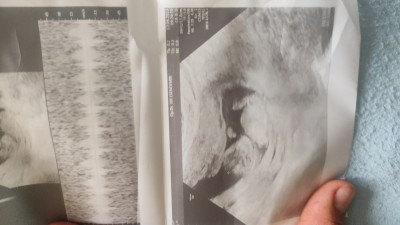

Cinsiyet tahmini kizlarr

Gebelik haftası 12+3 dogum